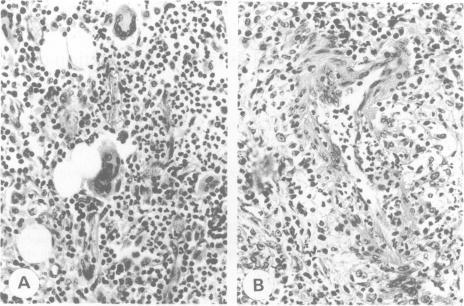

We describe a case of Wegener's disease with massive painful bilateral submandibular gland enlargement as the presenting symptom. The diagnosis was based on histologically documented nasal mucosa involvement, focal necrotizing glomerulonephritis, episcleritis and anti-neutrophil cytoplasmic antibody.

我们描述了一例以双侧下颌下腺无痛性肿大为首发症状的韦格纳肉芽肿病。诊断依据为组织学证实的鼻黏膜受累、局灶性坏死性肾小球肾炎、巩膜炎以及抗中性粒细胞胞浆抗体。